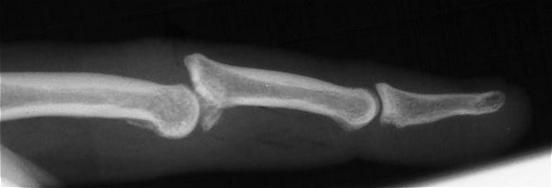

The most common type of middle phalanx base fracture is a small volar plate avulsion fracture, which commonly accompanies a sprain or dislocation of the proximal interphalangeal joint. This usually heals with a painless fibrous union. This injury requires no specific treatment other than what is indicated for the associated joint injury. Less common but much more troublesome are fracture-dislocations of the proximal interphalangeal joint. If the fracture line extends through the proper collateral ligament, the joint will become unstable, and the middle phalanx will displace with subluxation. Dorsal fracture-dislocations with a large palmar fragment are more common than volar fracture-dislocations. Either can be complicated by central articular impaction (Fig. 3). Treatment is controversial with advocates for internal or external fixation using a variety of techniques, including dynamic external traction, external fixation with distraction, internal fixation, and joint reconstruction with an osteochondral graft. Common principles include correction of subluxation, bone graft to correct impaction, and early motion.